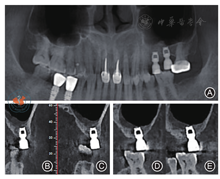

口腔卫生及25、26区牙龈状况良好,25附着龈宽约3 mm,26附着龈宽度约2.5 mm。术前CBCT示:25牙槽嵴宽约8 mm,高约9 mm,26牙槽嵴宽约7.5 mm,高约6.6 mm,左侧上颌窦内可见1个约29.7 mm × 20.4 mm,边界清楚、半圆形低密度影(图4)。

注:图4A为种植前囊肿大小;图4B~ 3C为种植前25牙槽嵴高度;图4D~ 3E为种植前26牙槽嵴高度,箭头示26颊侧骨质缺损